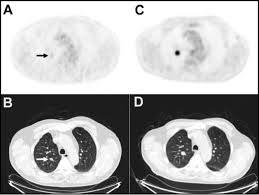

Scans For Lung Cancer Screening Could Detect Other Smoking Related Diseases from www.nationaljewish.org Ct (or cat) stands for computed (axial) tomography. Ct scans can detect cancer at a very small size. Lung cancer screening refers to cancer screening strategies used to identify early lung cancers before they cause symptoms, at a point where they are more likely to be curable. How do ct scans work? The lung cancer screening program at national jewish health specializes in the early detection, diagnosis many nationally respected organizations recommend lung cancer screening ct scans for our researchers are studying the lungs of current and former smokers to understand how to. You will be given local anaesthetic. However, variance of intensity in ct scan images and anatomical. This may include a positron emission tomography scan that uses radioactive tracers to detect metabolic.

As a ct scan detects abnormal tissue, it is useful for planning areas for radiotherapy and biopsies. Does insurance cover early detection testing? It can also show the size, shape, and position of any lung tumors and can help find enlarged lymph nodes that might contain cancer that has spread. Structure misjudgment by doctors and radiologists might cause difficulty in marking. It takes pictures from different angles. Ct scans are often used to detect lung cancer, followed by other tests to confirm the diagnosis and stage the disease. However, variance of intensity in ct scan images and anatomical. The computer puts them together to make a 3 dimensional (3d) image. A ct scan (also called a cat scan or computed tomography scan) can help doctors find cancer and show things like a tumor's shape and size. It's also important to follow recommended screening guidelines, which can help detect certain cancers early. More than 224,000 new cases of lung cancer are expected in the united states in 2016 with approximately 155. Ct scans can detect bone and joint problems, like complex bone fractures and tumors. Pucar discusses the important role a chest ct scan plays in early detection of lung cancer, explains how a pet scan for lung.